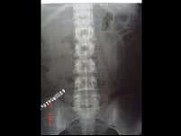

- 多项选择题女,28岁, 持续性腰痛加重2天,伴尿频、尿急、尿痛及发热, MRI如图所示,下列说法正确的是 ( )

A、单侧输尿管明显扩张,同侧的肾盂肾盏也扩张,但其程度轻于前者

B、考虑为先天性巨输尿管

C、考虑为输尿管下端结石并积水

D、考虑为输尿管癌所致的梗阻积水

E、考虑为输尿管囊肿